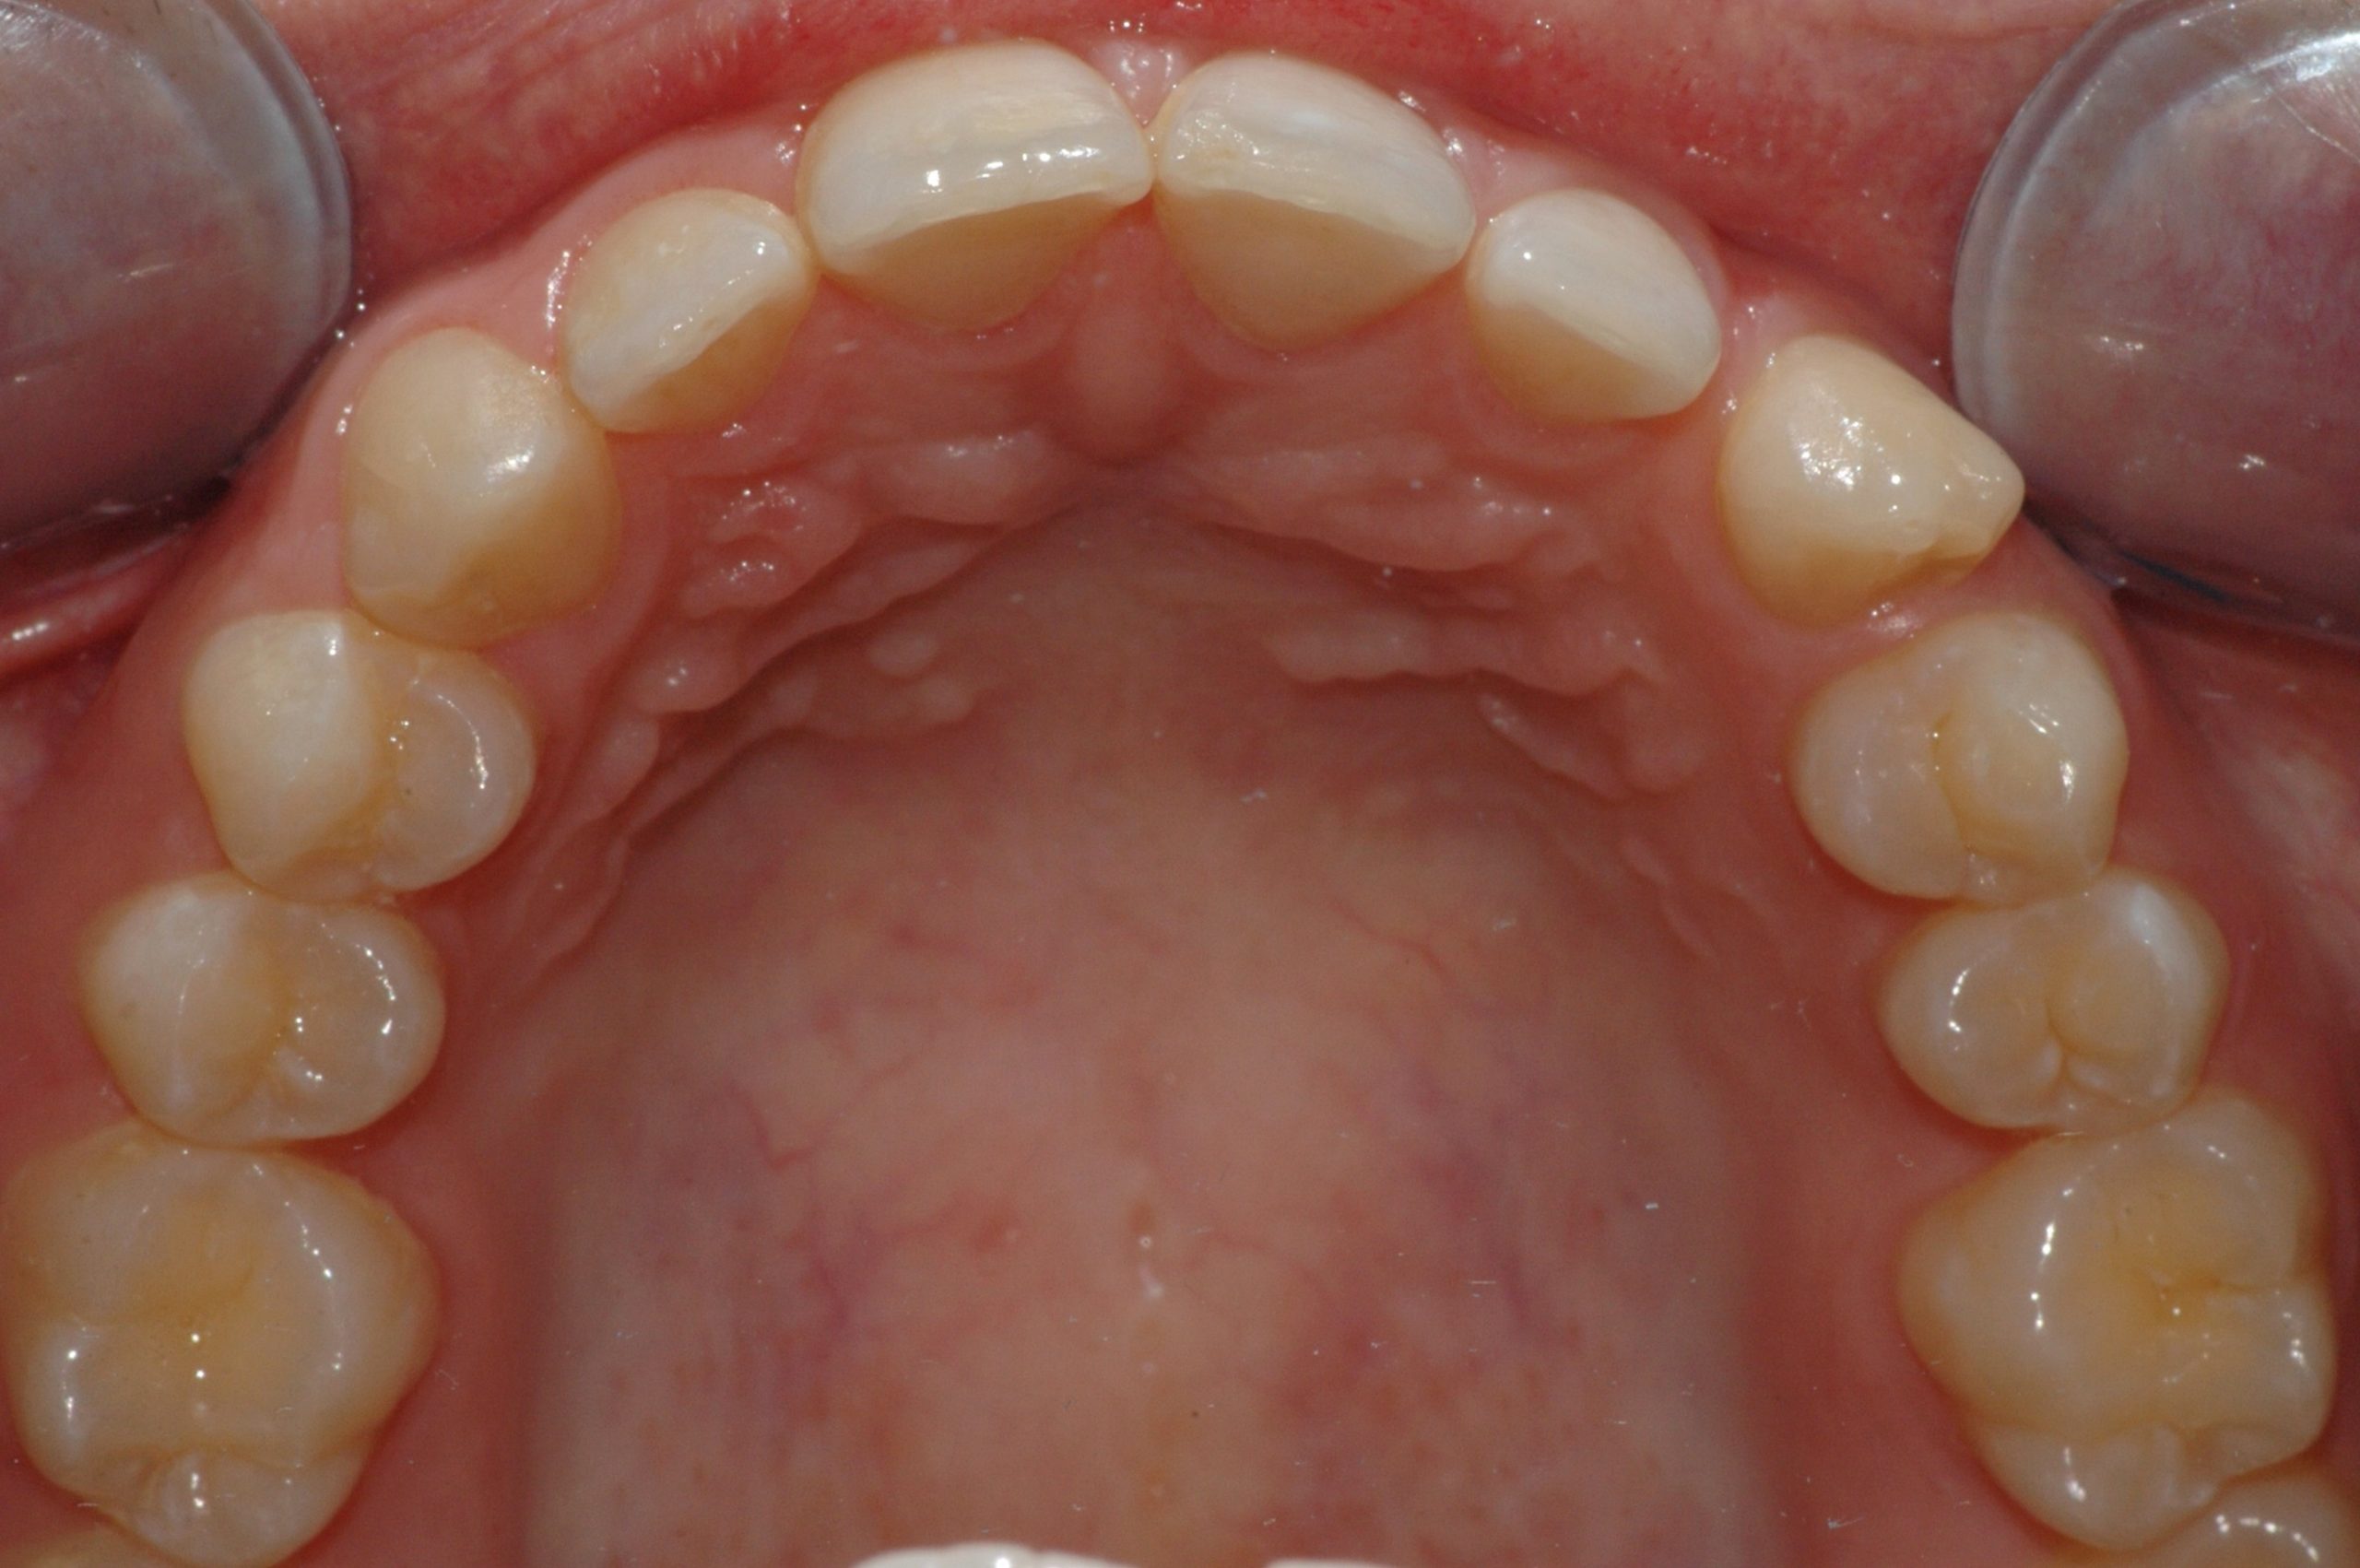

Caso clinico

La paziente presenta malposizione degli incisivi antero-superiori, in particolare un forte sventagliamento degli incisivi laterali. In seguito a trattamento con allineatori trasparenti, durato 9 mesi, si è ottenuto un allineamento pienamente soddisfacente.

PRIMA

DOPO